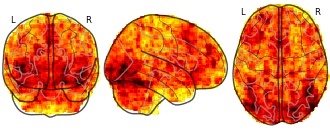

"name": "Multi_VBMgreater_fMRIenhanced",

"description": "Multi-modal analysis in BPD. Brain regions exhibiting greater gray matter and enhanced activation during emotion processing in BPD compared to healthy controls. Note: Results were thresholded at p<.0025. Note2: Results were updated (see Erratum for this publication).",

"name": "Multi_VBMsmaller_fMRIenhanced",

"description": "Multi-modal analysis in BPD. Brain regions exhibiting smaller gray matter and enhanced activation during emotion processing in BPD compared to healthy controls. Note: Results were thresholded at p<.0025. Note2: Results were updated (see Erratum for this publication).",